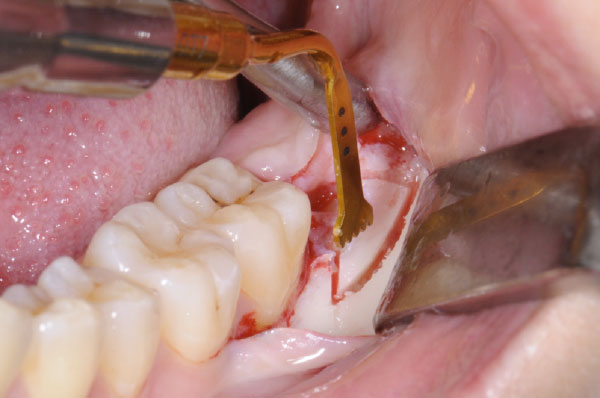

L'intervento segue precisi protocolli chirurgici. Dopo l'esecuzione di un'anestesia loco-regionale, si procede all'allestimento di un lembo di accesso mucoperiosteo a spessore totale, la cui scelta è determinata principalmente dalla profondità dell'inclusione e dalla posizione del terzo molare. In tutti i casi, il lembo deve creare un sufficiente accesso chirurgico (visivo e strumentale), evitare le strutture anatomiche circostanti (nervo linguale, arteria facciale), consentire un corretto riposizionamento del lembo e un'agevole sutura.

L'utilizzo dello strumentario piezoelettrico rappresenta una valida alternativa nei casi di ostectomia profonda e per l'avulsione di residui radicolari in stretto rapporto con strutture anatomiche nobili.